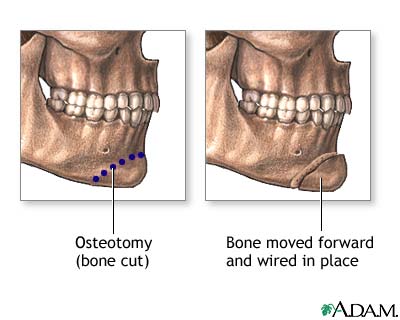

The surgeon may also need to move some bones:

- You will likely be under general anesthesia.

- The surgeon will make a cut inside your mouth along the lower gum. This gives the surgeon access to the chin bone.

- The surgeon uses a bone saw or chisel to make a second cut through the jaw bone. The jaw bone is moved and wired or screwed in place with a metal plate.

- The cut is closed with stitches and a bandage is applied. Because the surgery is performed inside your mouth, you will not see any scars.